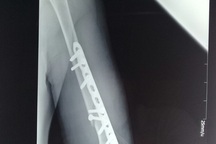

Tuy nhiên, phía công ty không làm hợp đồng cung cấp dịch vụ mà chỉ thỏa thuận miệng. Ngày 1/7/2018 tai nạn xảy đến “khi nhân viên tên Sang (không rõ họ) của công ty Nhã Hương đang thực hiện kỹ thuật vật lý trị liệu cho cha tôi, đến khi bẻ cánh tay trái thì nghe tiếng “rắc”. Thấy cha đau đớn, chúng tôi đã đưa đến Bệnh viện Nhân Dân Gia Định, bác sĩ xác định ông gãy kín 1/3 dưới xương cẳng tay trái phải phẫu thuật kết hợp xương. Sau vị việc, phía Công ty Nhã Hương không có động thái hợp tác mà muốn chối bỏ trách nhiệm.